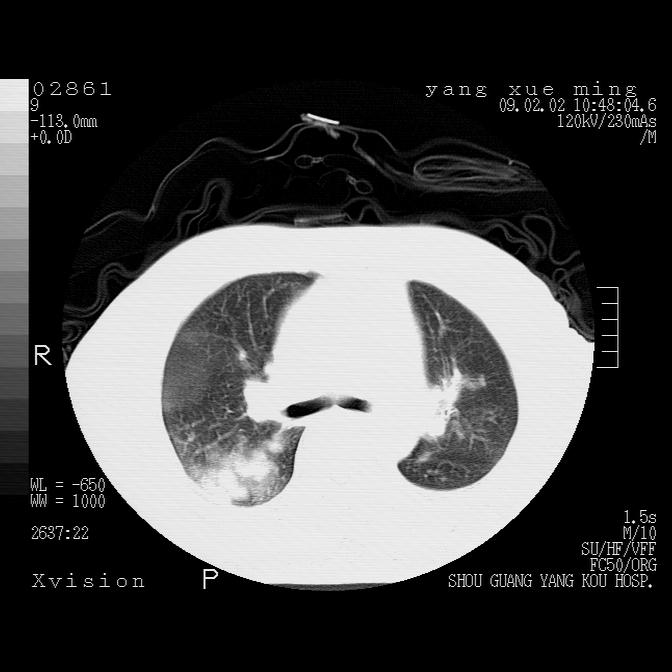

以下是引用zbp537在2009-2-3 19:08:00的发言:[br]我诊断为肺泡性肺水肿。[br]诊断依据:[br]1、心影普遍增大,肺血管增粗,并见絮状高密度影,肺门改变显著。[br]2、临床上表现胸闷咳嗽,无发烧,不是一个典型的肺部感染的病史。

以下是引用lkc8963在2009-2-3 20:11:00的发言:[br]1)右上肺陈旧病灶。2)右下肺团块及团片影,影像表现符合感染。3)左心增大,左冠脉钙化,符合冠心病。4)双侧肺门扩大,以左侧为著,肺动脉干略粗,左上肺局限性气肿,为谨慎起见,需除肿瘤,建议增强。

以下是引用lkc8963在2009-2-3 20:11:00的发言:[br]1)右上肺陈旧病灶.2)右下肺团块及团片影,影像表现符合感染.3)左心增大,左冠脉钙化,符合冠心病.4)双侧肺门扩大以左侧为著,肺动脉干略粗,左上肺局限性气肿,为谨慎起见,需除肿瘤,建议增强.